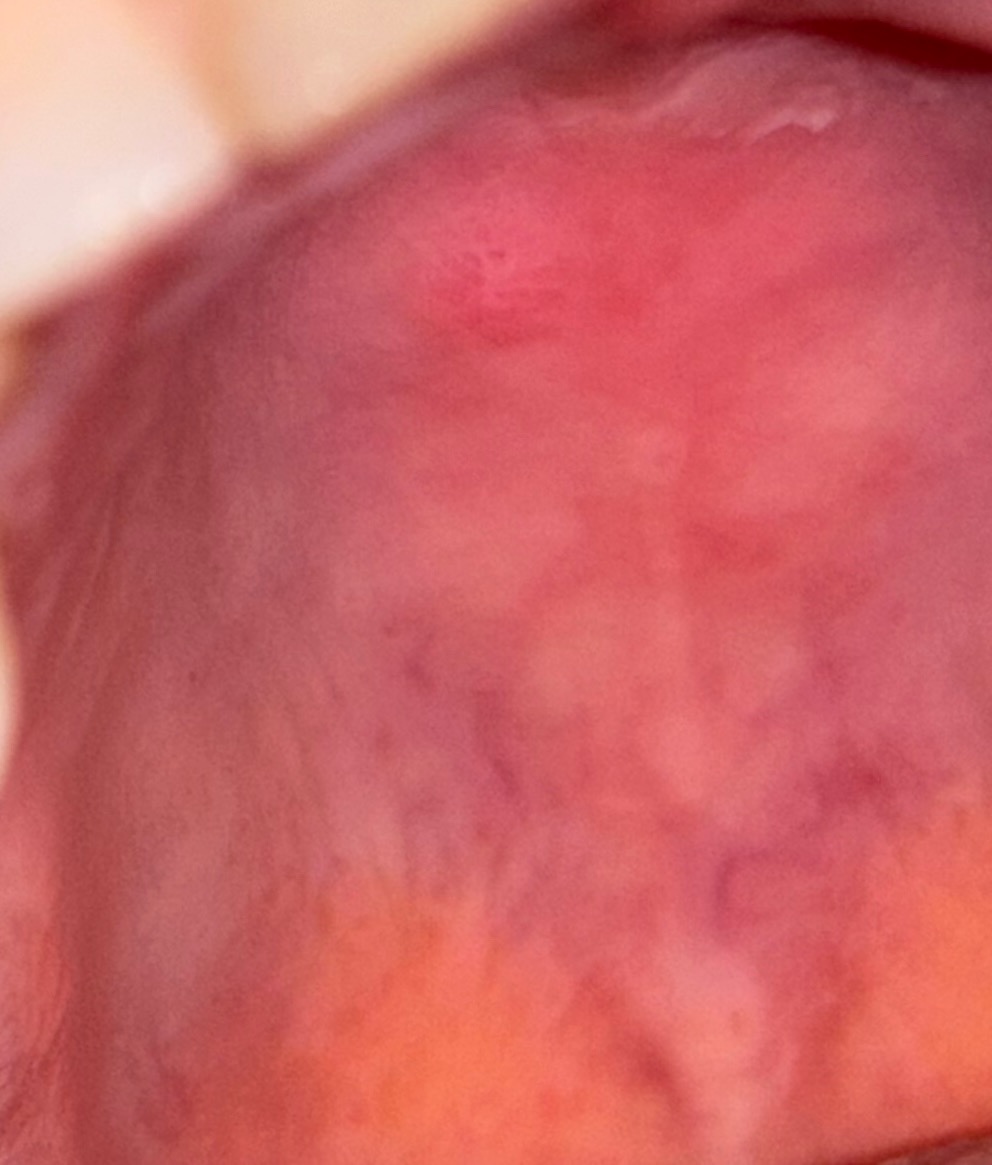

Hallo. Hane die Beule schon seid einen Monat. Sie ist hart und schmerzt bei Druck.Was kanm das sein?

die Beule ist immer noch da, ich denke sie hat sich ein wenig verändert. Ist sie immernoch harmlos?